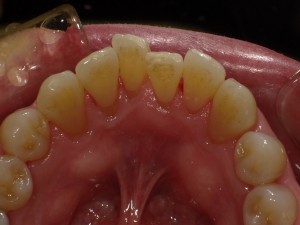

下の写真は下顎の前歯の内側を写した物です。左の写真は歯石の沈着が見られます。

右は綺麗に除去した後の写真です。